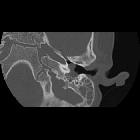

congenital cholesteatoma

cholesteatoma • Petrous apex cholesteatoma - Ganzer Fall bei Radiopaedia

Congenital cholesteatomas are identical to epidermoid cysts, differing only in name and location.

They are intraosseous inclusions of ectoderm and are therefore comprised of keratin debris and cholesterol. Characteristically, they are located at the petrous apex. In contrast, middle ear cholesteatomas tend to be acquired, secondary to tympanic membrane perforation.

MRI shows sharply demarcated margins with smooth bony erosions.